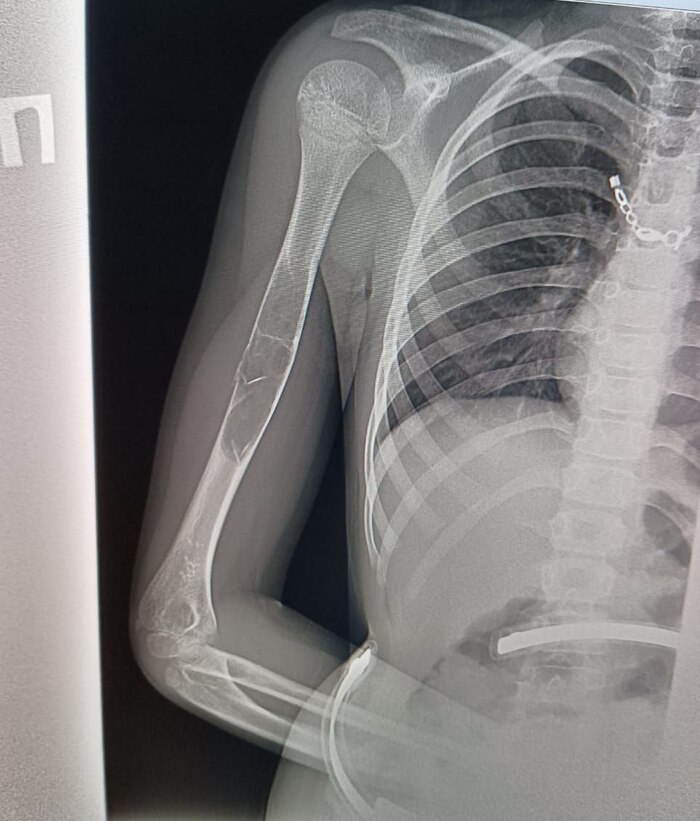

Нужны мнения травматологов и хирургов

Петербург. Девочка, почти 9 лет, легкий сколиоз. Падение с велосипеда, RG руки, результат

Имеем патологический перелом, причина - предположительно, фиброзная дисплазия или аневризмальная киста кости.

Рекомендованный план лечения: 6 недель в гипсе по турнеру, полное заживление перелома и образование костной мозоли, потом КТ и дифдиагностика, подготовка и операция по удалению всего образования.

После проведённых исследований обязательно соберу мнения в Турнера и Педиатричке.

Врачи говорят, что зоны роста почти не задеты, есть шанс полного восстановления здоровья и полноценной дальнейшей жизни.